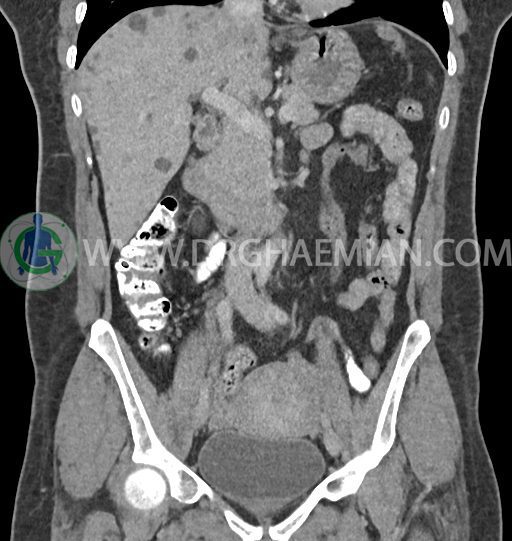

سی تی اسکن شکم و لگن با استفاده از اشعات ایکس تصاویر عرضی از ناحیه شکم و لگن ایجاد میکند. در این کیس کبد پلی کیستیک، کیست در تخمدان چپ، توده در دیواره سرویکس و اسپوندیلولایزیس دو طرفه مهره L5 دیده می شود.

در سی تی اسکن اسپیرال شکم و لگن – 5Phasic (بدون کنتراست – با کنتراست در فاز آرتریال ، پورتال و تاخیری 5 دقیقه و 10 دقیقه، مولتی دیدکتور 16 با مقاطع ظریف و بازسازی های ساژیتال و کرونال) :

-ضایعات سیستیک فراوان به قطر 5 تا 30mm پراکنده در کبد بدون جزء سالید، بدون septation و بدون اینهنسمنت پس از تزریق کنتراست مطرح کننده polycystic liver disease

-کیست ساده به قطر 31mm در تخمدان چپ

-توده هیپودنس به قطر 13mm در دیواره قدامی سرویکس نیازمند مطابقت سونولوژیک

-اسپوندیلولایزیس دو طرفه L5 همراه با آنترولیستزیس gread 1 و تغییرات DJD در L5/S1

مشهود است.